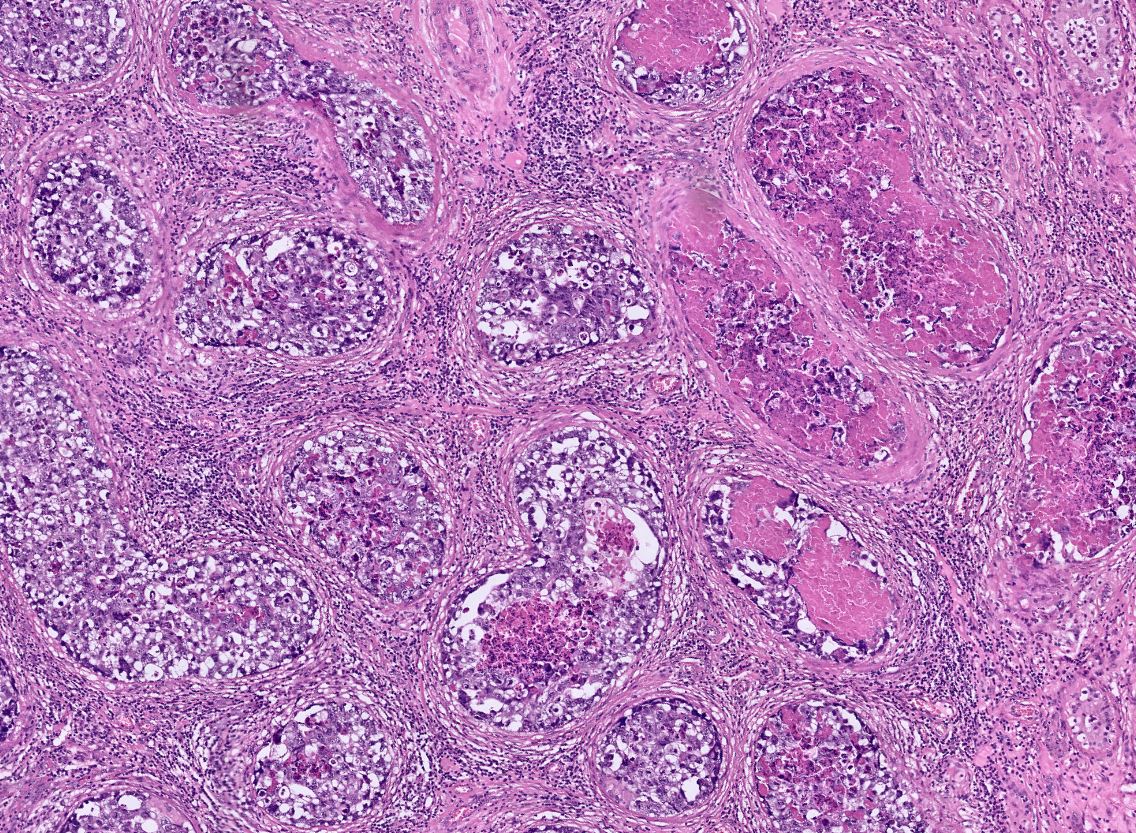

#Breastpath #Surgpath #Pathresidents #Pathtwitter Resection of a suspicious breast mass in a 60 year old woman. Take a look at some images, place your vote, and read some discussion.

BrownPathology's tweet image. #Breastpath #Surgpath #Pathresidents #Pathtwitter

Resection of a suspicious breast mass in a 60 year old woman.  Take a look at some images, place your vote, and read some discussion.